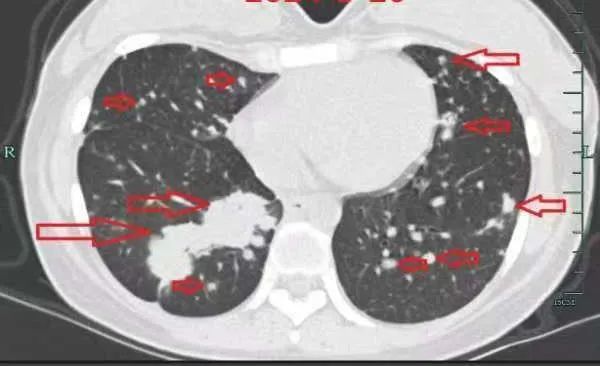

治疗后

几个月后,她的病情逐渐好转,肺部的“满天星”也消失了!小谢满心感激:“是丁主任救了我的命,让我重获新生!”